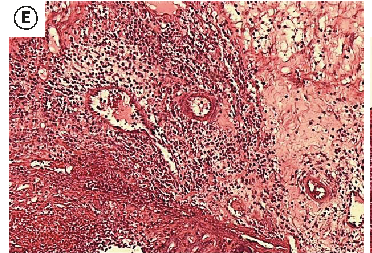

Figure 6

The Healing Effect of Aloe Vera Gel on Acetic Acid-Induced Ulcerative Colitis …